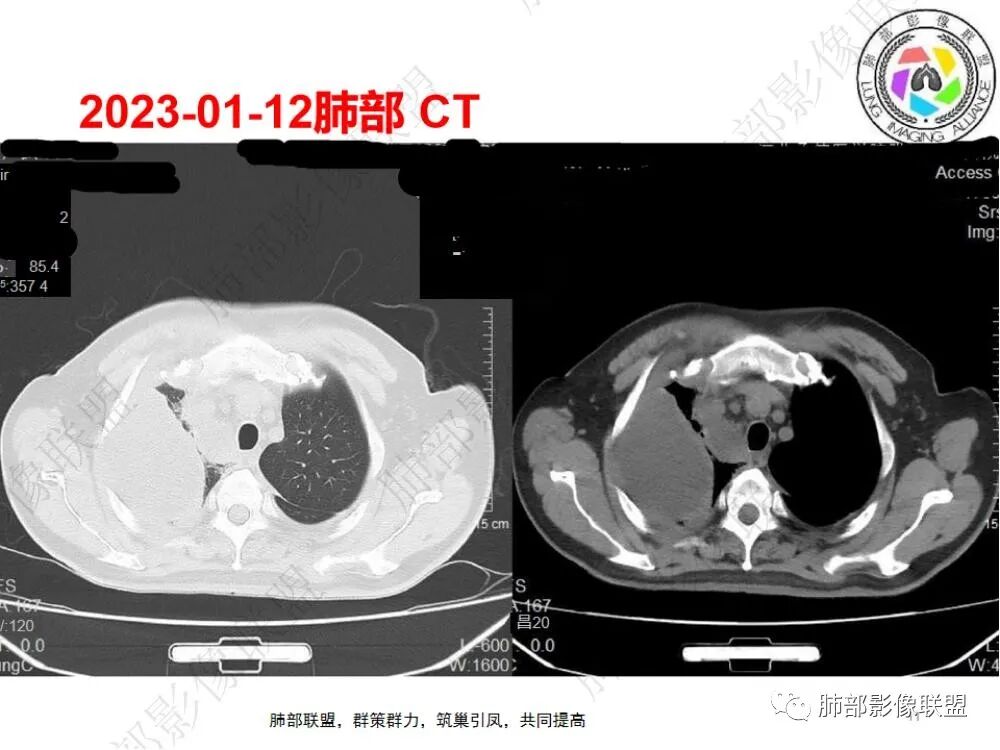

刘波:

中老年男性,发热,咳痰10天,加重5天,糖尿病病史,要考虑到糖尿病合并肺部感染四大金刚(金葡菌、毛霉菌、结核、肺炎克雷伯杆菌),C反应蛋白及白细胞明显增高,PCT增高至44.34,这个至可以考虑到脓毒症(尤其阴性菌)。2023-1-5日片,双肺多发斑片状/片子密度增高影,边缘相对较清晰/膨隆,右肺较明显,病灶内见支气管影,小支气管未见明确现实;病灶似有重力依赖,背侧明显较实,右侧胸腔见散在包裹性积液;2023-1-12,间隔一周,包裹性积液改变增多,右肺中叶外压行膨胀不全;右肺下叶病灶明显液化坏死,可以考虑肺克可能大。

6.一周后复查变化较为明显。肺部实变影有所吸收,但胸腔积液增加明显,包裹于侧胸壁、纵隔旁及叶间裂。注意右肺下叶因积液推压明显(可惜未能提供薄层图片及矢状位图片)。